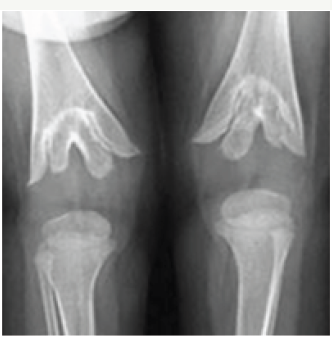

Radiological findings of nutritional rickets are almost the same in other forms of rickets. In the Differential diagnosis, Hypophospatasia (low serum alkaline phosphatase) and metaphyseal chondrodyplasia (type schmid). Hypophospatasia may be encountered in neonates, children, adolescents and adults. Radiographics manifestations are different according to ages [7]. Deep cupping with irregularity of metaphyses is a common finding in children, simulating healing rickets (Figure 6).

Figure 7: Metaphyseal dysplasia simulating rickets.

Metaphyseal chondrodysplasia is a rare genetic abnormality with no Vitamin D abnormality. There is generalized symmetric disturbance of enchondral bone formation. Radiologically, the metaphysic are well mineralized and may have increased density with irregular margins, simulating healing rickets7. Serum calcium, phosphorus and alkaline phosphatase are normal (Figure 7).